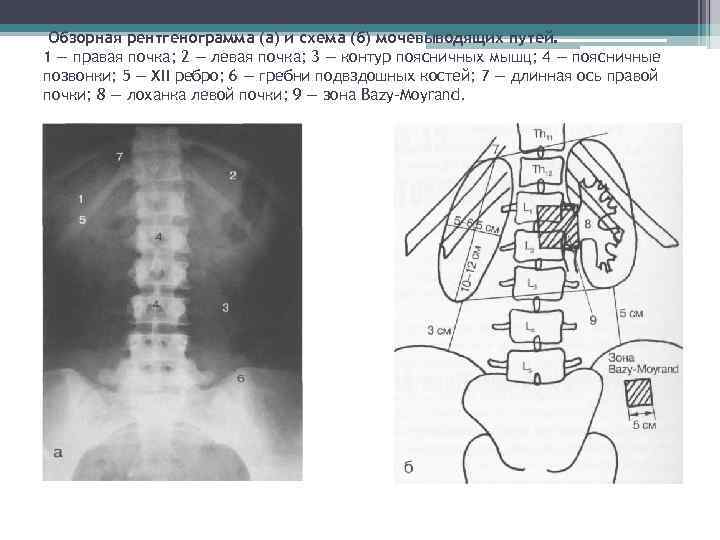

Обзорная рентгенограмма области живота Предназначена для выявления конкрементов, обызвествлений и газов.

Обзорная рентгенограмма (а) и схема (б) мочевыводящих путей. 1 — правая почка; 2 — левая почка; 3 — контур поясничных мышц; 4 — поясничные позвонки; 5 — XII ребро; 6 — гребни подвздошных костей; 7 — длинная ось правой почки; 8 — лоханка левой почки; 9 — зона Bazy-Moyrand.